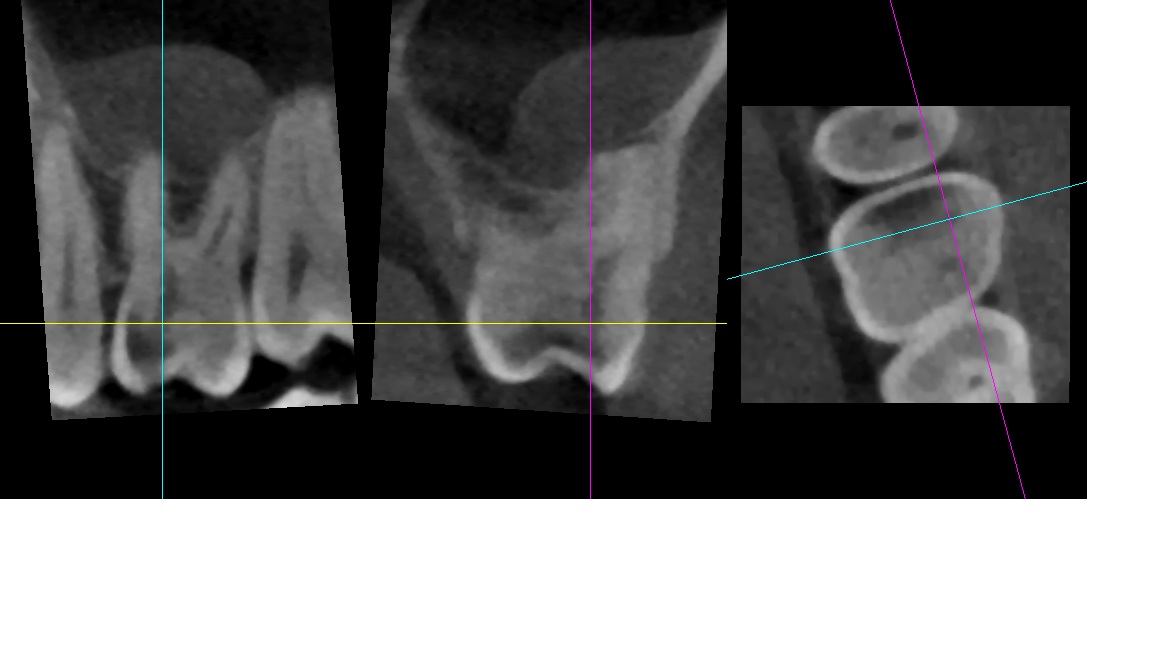

We use rotary nickel-titanium instruments, activated irrigation for deep disinfection, and modern bioceramic sealers for a dense, long-lasting seal. - Targeted diagnostics

We examine the tooth, test its response, and take focused images. When roots are complex or a previous treatment failed, a small 3D scan may be needed for mapping before we discuss and agree on the plan. - Anaesthesia and comfort